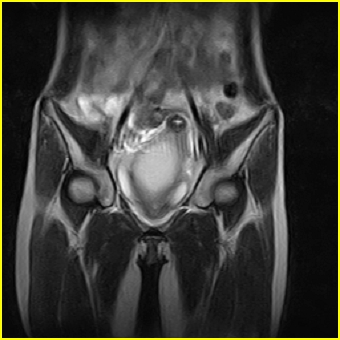

女、15岁、下腹疼痛2天,排尿困难1天。查体:处女膜闭锁,距处女膜约4至5cm处扪及一约5cm直径的圆形包块,张力较高,触痛明显、欠活动。b超提示子宫增大伴宫内增强回声团。

影像意见:子宫直肠陷凹积血。

更正影像意见:阴道积血。

处女膜闭锁,阴道积血

处女膜闭锁,阴道积血,子宫积血.

阴道积血,子宫积血.

子宫及阴道积血。

处女膜闭锁,伴子宫及阴道积血.